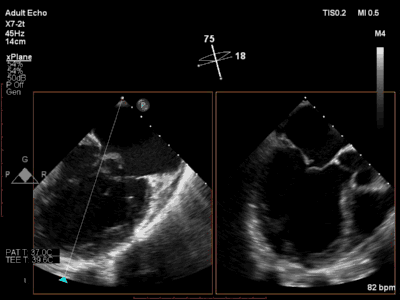

患者术前心超显示极重度反流